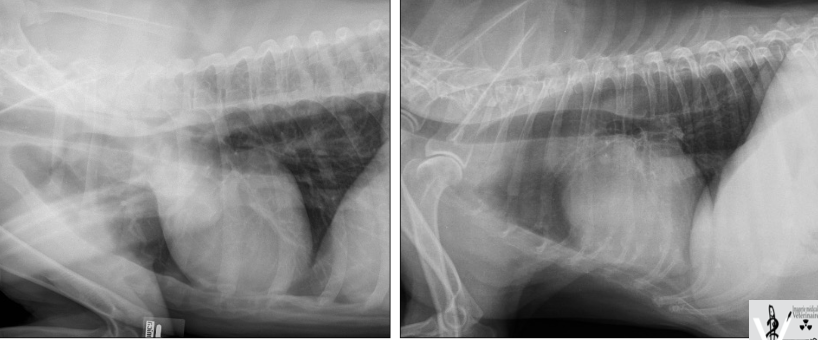

Nommez les opacités de chaque lettre.

a) métal

b) gras

c) minérale

d) air

e) tissu mou